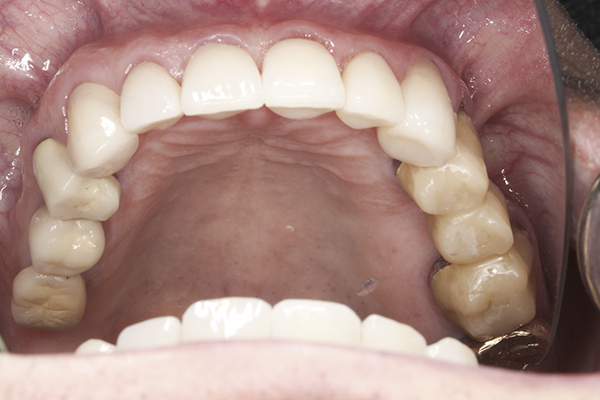

(41.) Postoperative maxillary occlusal view. Note the composite tops on teeth Nos. 12 through 14.

Figure 41